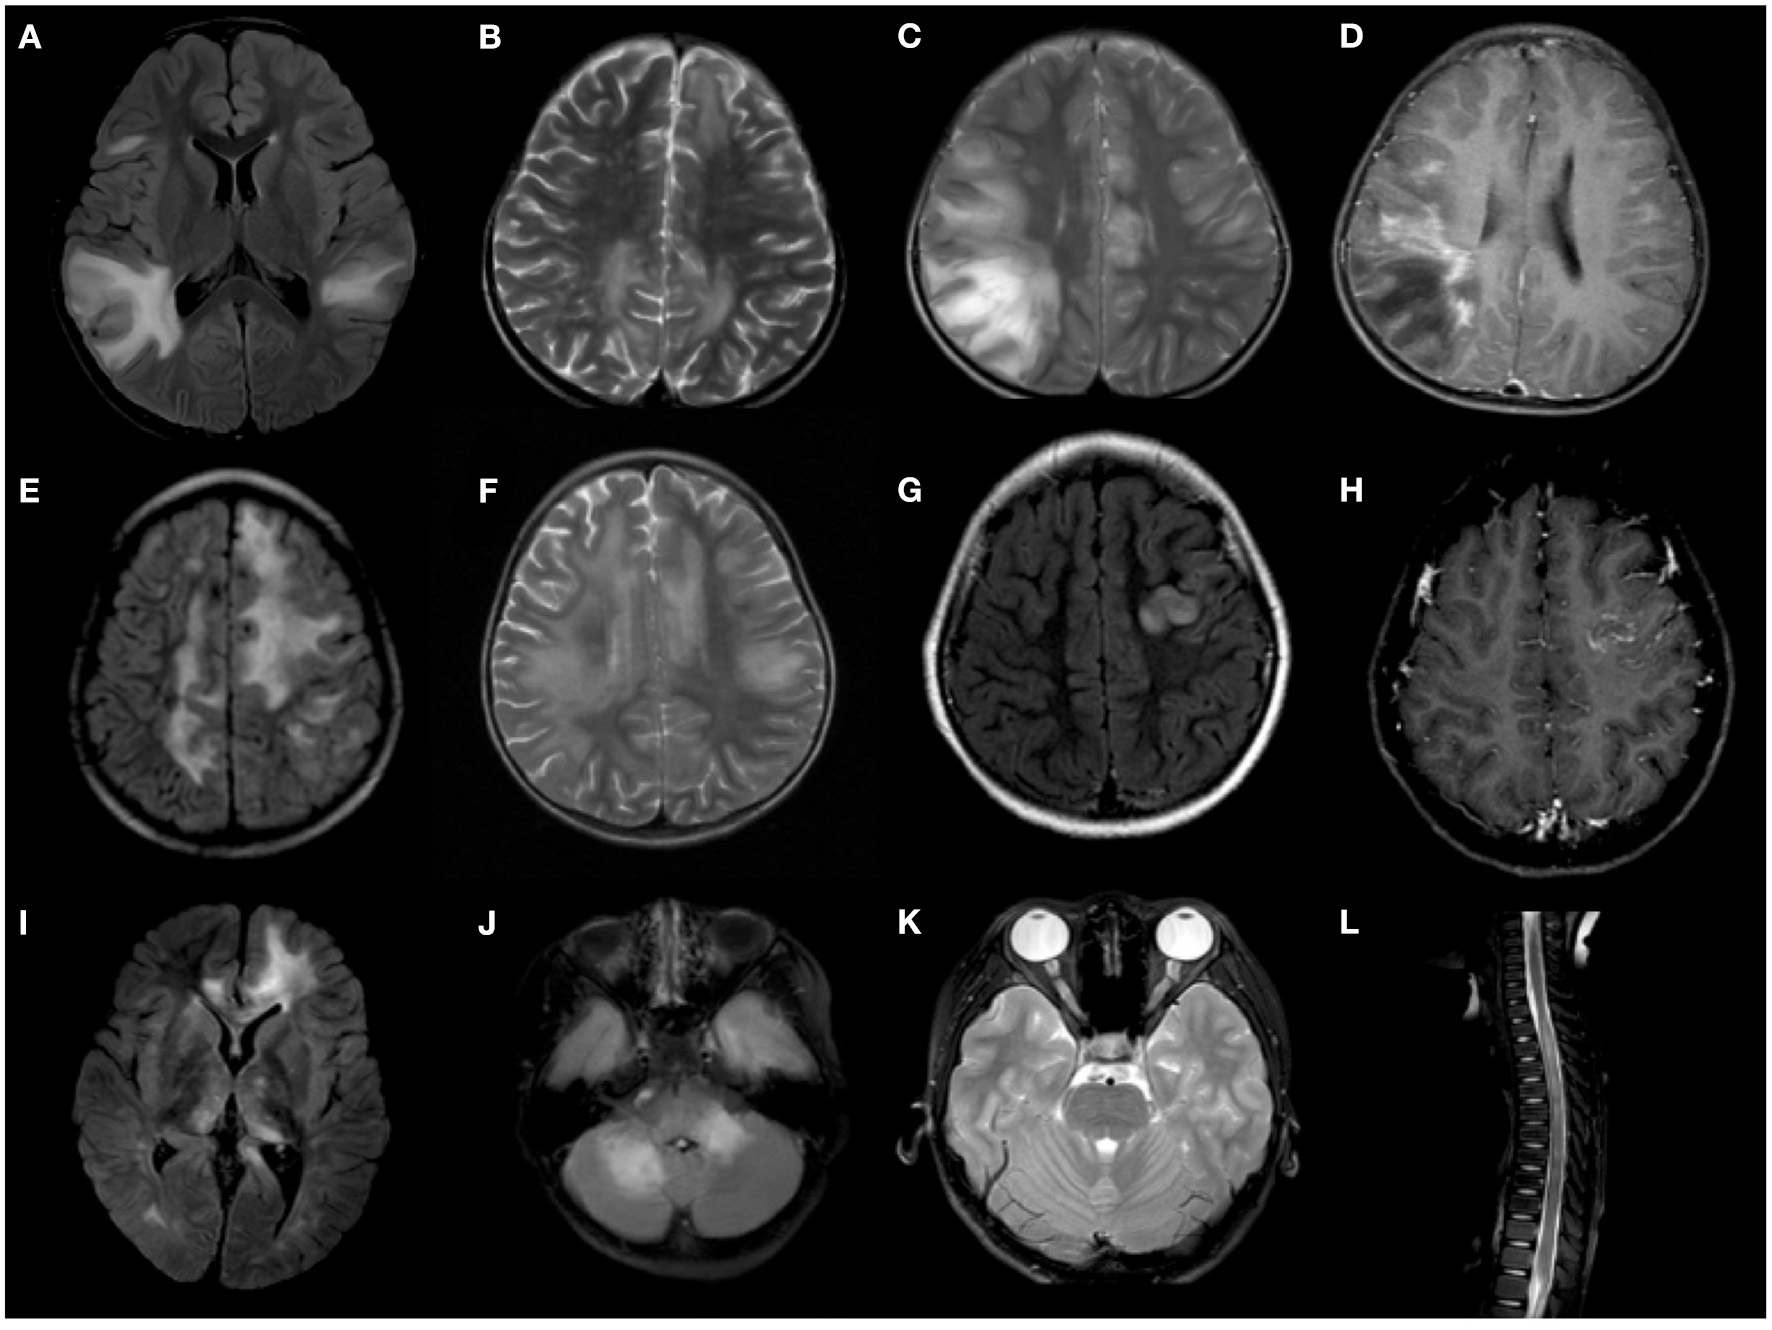

MOG-ab-positive patients tended to have bilateral lesions and deep gray matter involvement more often than AQP4-ab-positive patients (p = 0.032 and p = 0.038, respectively) on brain MRI. However, spinal involvement was more common in AQP4-ab-positive patients than in MOG-ab-positive patients (p = 0.027), and cervical and thoracic segment involvement was more distinct on spinal MRI (p = 0.018 and p = 0.008, respectively). However, there were no differences in the location and enhancement between the two cohorts on orbital MRI (Table 3). Figure 2 shows representative radiological images of MOG-ab–positive patients.

Figure 2

Representative radiological features of MOG-ab-positive patients. (A–D) Confluent, poorly demarcated lesions in gray and white matter. (E,F) Extensive, confluent, essentially symmetric white matter lesions (leukodystrophy-like). (G,H) Unilateral cortical lesion. (I) Deep gray matter involvement. (J) Cerebellum and cerebellar peduncle lesions. (K) Bilateral optic nerve involvement. (L) longitudinally extensive transverse myelitis (LETM).